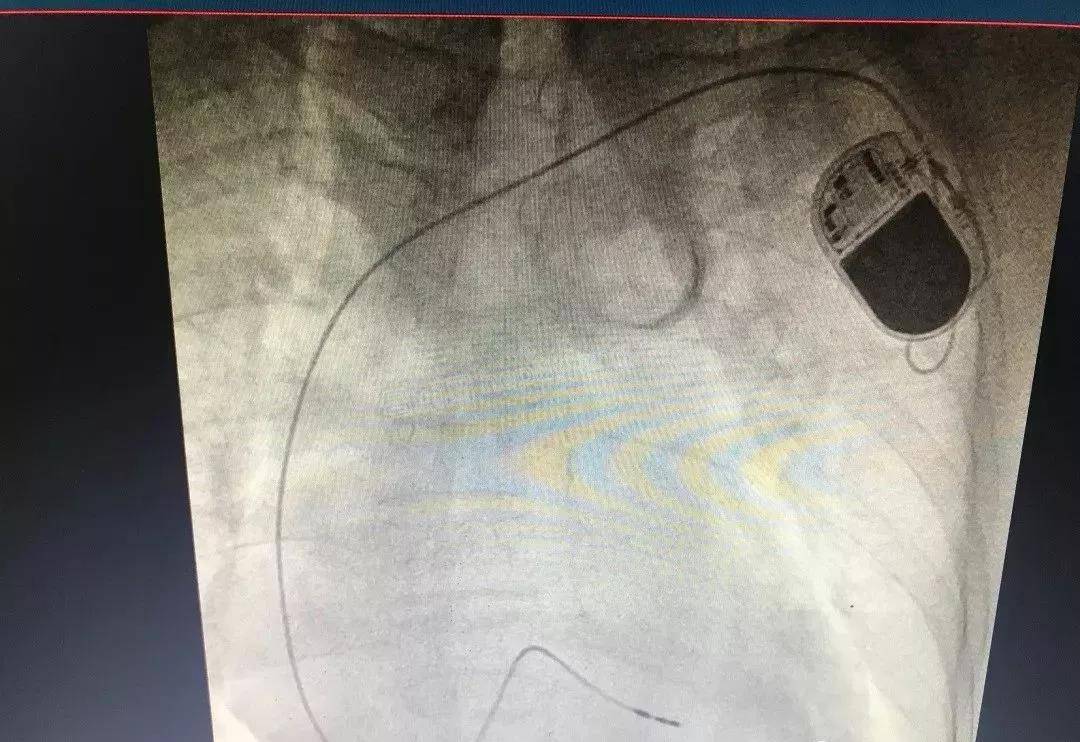

合浦人民医院普外二区开展肝肿瘤介入治疗以来,已让众多肝癌中晚期患者受益,为他们带来了新的希望。 胸腰椎椎体压缩性骨折椎体成形术是在DSA引导下,用经皮穿刺的方法,用球囊被压缩的椎体撑开恢复高度后将骨水泥注入,从而达到被压缩椎体高度复原、增强椎体强度和稳定性 、防止塌陷、疼痛部分或完全缓解的目的。它具有创伤小,将穿刺针插入椎体即可;安全性高,无严重并发症;疗效肯定,患者术后即刻或几天内腰背痛症明显减轻或消失,并且疗效可长期维持等优点。

胸腰椎骨折可造成局部疼痛,活动障碍,甚至引起下肢瘫痪。老年人因骨质疏松导致椎体压缩性骨折已屡见不鲜,对病人的生活带来极大的不便。如果椎体压缩骨折较轻的话,一般可以通过保守治疗,但需卧床3个月,长期卧床可以导致呼吸系统感染、泌尿系统感染、褥疮等一系列并发症。严重者则需要手术治疗,手术通常的方法为切开复位内固定,手术创伤大,出血多,并有切口感染,内固定松动等风险。 我院骨科一区开展微创技术治疗胸腰椎压缩性骨折,创伤小、止痛快。术后患者疼痛及坐卧行走功能即刻得到显著的改善:术后镇痛有效率达70-90%;病人常可1-3天内坐、站及行走,极大地提高患者的生活质量。术后一般只需要住院观察几天,既减少了患者的经济负担,又减轻了家庭及社会的负担。